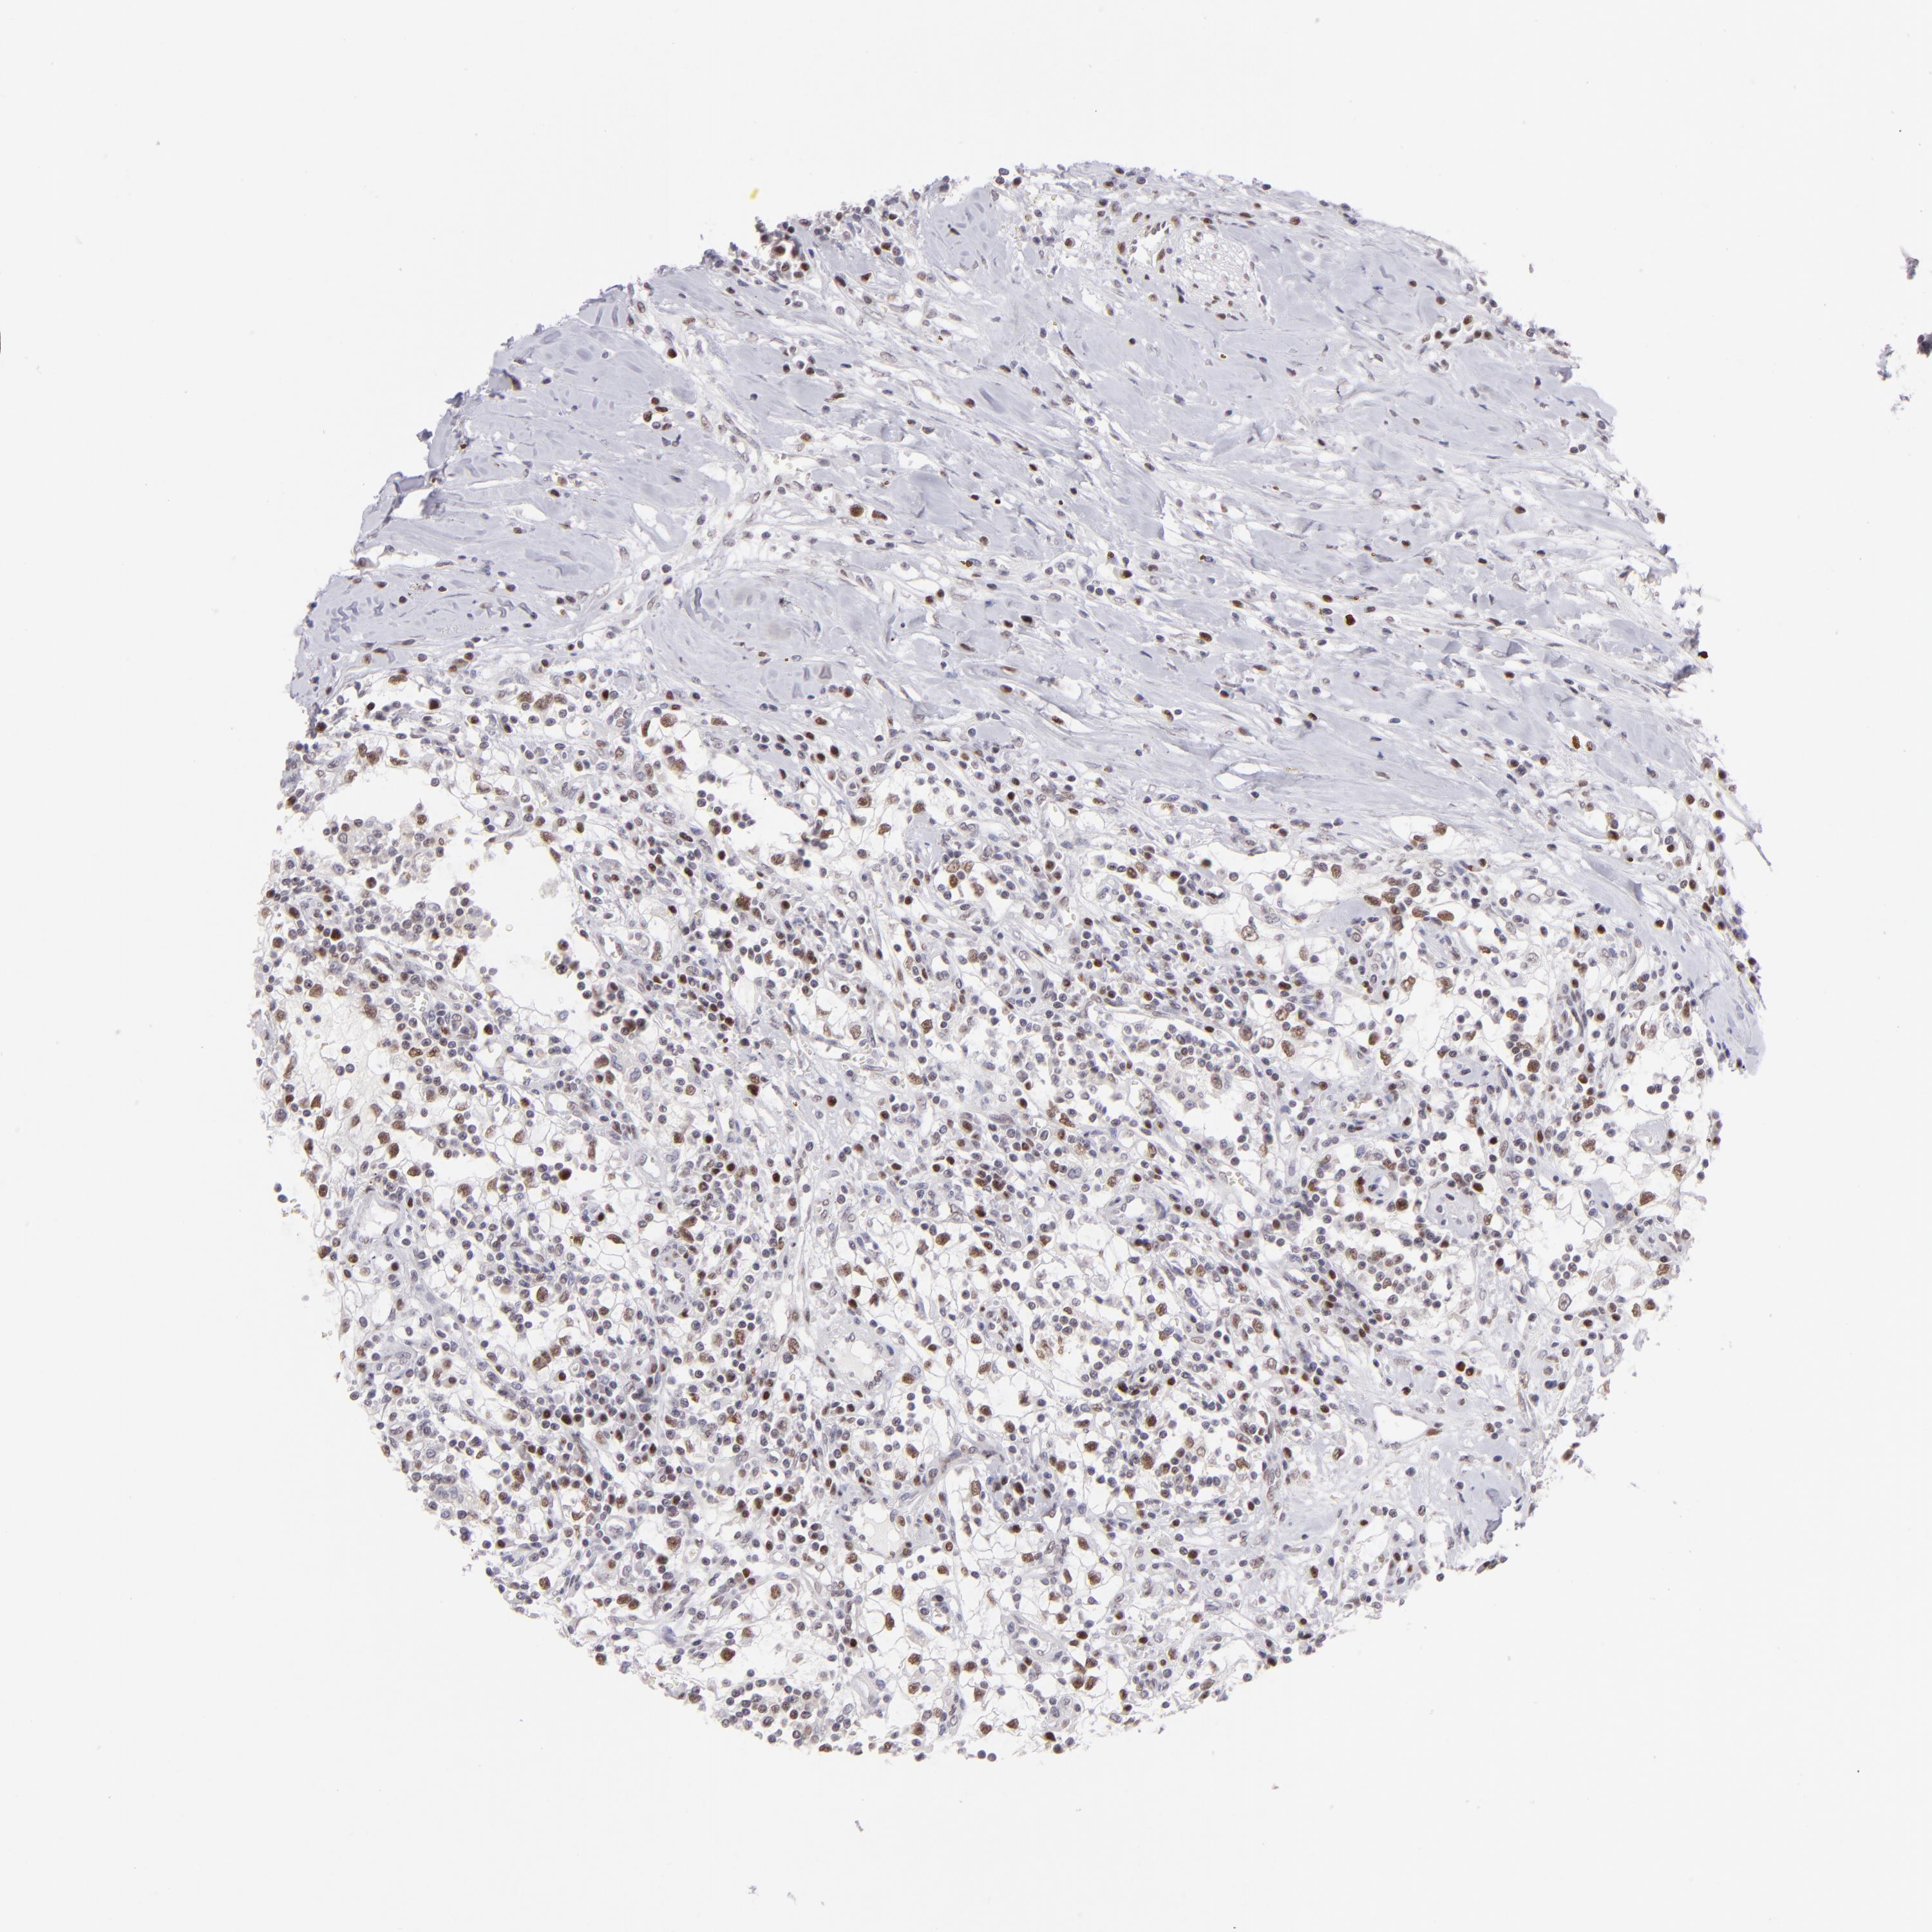

KIDNEY RENAL CLEAR CELL CARCINOMA (VALIDATION) - Interactive survival scatter ploti

The Survival Scatter plot shows the clinical status (i.e. dead or alive) for all individuals in the patient cohort, based on the same data that underlies the corresponding Kaplan-Meier plots. Patients that are alive at last time for follow-up are shown in blue and patients who have died during the study are shown in red.

The x-axis shows the expression levels (FPKM) of the investigated gene in the tumor tissue at the time of diagnosis. The y-axis shows the follow-up time after diagnosis (years). Both axes are complimented with kernel density curves demonstrating the data density over the axes. The top density plot shows the expression levels (FPKM) distribution among dead (red) and alive patients (blue). The right density plot shows the data density of the survived years of dead patients with high and low expression levels respectively, stratified using the cutoff indicated by the vertical dashed line through the Survival Scatter plot. This cutoff is automatically defined based on the FPKM cutoff that minimizes the p-score. The cutoff can be changed by dragging the vertical line or by entering a cutoff value in the square labeled "Current cut-off".

Under the Survival Scatter plot the p-score landscape (black curve; left axis) is shown together with dead median separation (red curve; right axis). Dead median separation is the difference in median mRNA expression between patients who have died with high and low expression, respectively. It is calculated as follows: median FPKM expression of dead patients with high expression - median FPKM expression of dead patients with low expression. This is intended to aid the user in visually exploring custom cutoffs and the associated p-scores and dead median separation.

Individual patient data is displayed and can be filtered by clicking on one or more of the category buttons on the top of the page. Categories describing expression level and patient information include: high, low, alive, dead, female, male and tumor stages. The scale of the x-axis can be toggled between linear and log-scale by clicking on the "x log" button. Mouse-over function shows TCGA ID, patient information and mRNA expression (FPKM) for each patient.

& Survival analysisi

Kaplan-Meier plots summarize results from analysis of correlation between mRNA expression level and patient survival. Patients were divided based on level of expression into one of the two groups "low" (under cut off) or "high" (over cut off). X-axis shows time for survival (years) and y-axis shows the probability of survival, where 1.0 corresponds to 100 percent.

POU2F1 is not prognostic in Kidney Renal Clear Cell Carcinoma (validation)

Best expression cut offi

Based on the FPKM value of each gene, patients were classified into two groups and association between prognosis (survival) and gene expression (FPKM) was examined. The best expression cut-off refers the FPKM value that yields maximal difference with regard to survival between the two groups at the lowest log-rank P-value. Best expression cut-off was selected based on survival analysis .

When clicking on this number, the vertical dashed line indicating cut-off, the interactive survival plot, and the Kaplan-Meier curve will be adjusted to show results based on the best expression cut-off.

: 3.37

Median expressioni

Median expression refers to the median FPKM value calculated based on the gene expression (FPKM) data from all patients in this dataset. When clicking on this number, the vertical dashed line indicating cut-off, the interactive survival plot, and the Kaplan-Meier curve will be adjusted to show results based on the median expression.

: N/A

Median follow up timei

Median follow up time refers to the median time (years) after diagnosis with this type of cancer, based on clinical data from all patients in this dataset.

P scorei

Log-rank P value for Kaplan-Meier plot showing results from analysis of correlation between mRNA expression level and patient survival.

N/A

5-year survival highi

5-year survival for patients with higher expression than the expression cutoff.

For melanoma and glioma, 3-year survival is shown.

5-year survival lowi

5-year survival for patients with lower expression than the expression cutoff.

TCGA RNA samplesi

RNA-seq data is reported as average FPKM (number Fragments Per Kilobase of exon per Million reads), generated by the The Cancer Genome Atlas (TCGA) .

Normal distribution across the dataset is visualized with box plots, shown as median and 25th and 75th percentiles. Points are displayed as outliers if they are above or below 1.5 times the interquartile range. FPKM values of the individual samples are presented next to the box plot.

Average pTPM 3.2

Number of samples 100